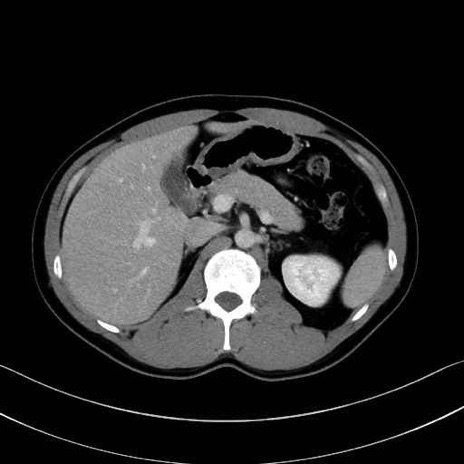

【症例】20歳代 男性 スクリーニング

■起始:典型的には腹腔動脈幹(celiac trunk)から左胃動脈・総肝動脈とともに三分岐し、脾動脈は左後上方へ向かう。

■走行:膵上縁または膵実質背側を蛇行しながら左方へ進み、膵尾部近傍で脾門へ至る。蛇行の程度は個体差が大きい。

■終枝:脾門部で複数の終末枝に分かれ、上極・下極枝や脾門枝群を形成する。胃短動脈群や左胃大網動脈はしばしば脾動脈から分岐する。